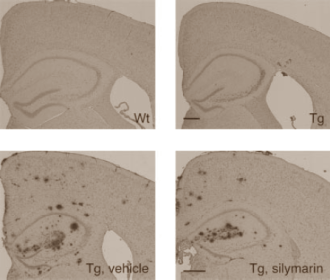

The photos above show samples of brain tissue. The upper row shows tissue from mice at the start of supplementation. The bottom row shows brain tissue from Alzheimer's mice aged one year. The dots are plaques.